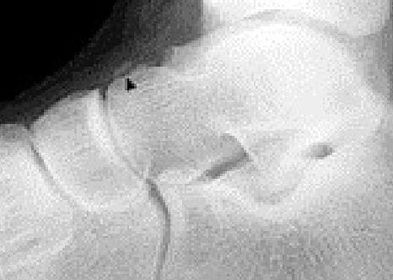

Describe what the arrows are showing | Torus fracture of the 1st met. "Buckling" of the proximal one third diaphysis is seen both medially and laterally. Common in paediatric patients |